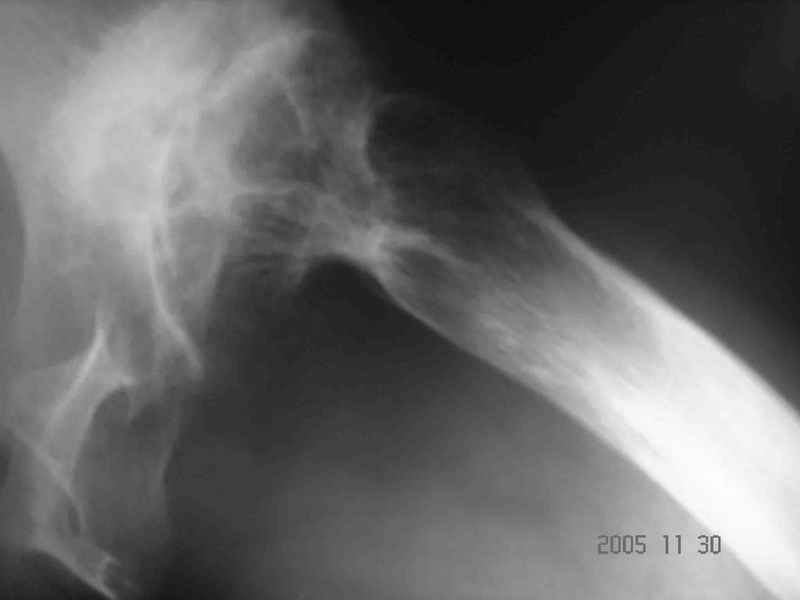

Аксиальный Р-снимок

Вы вполне можете обойтись стандартной клиновидной ножкой, определенные сложности будут в установке вертлужного компонента. Если есть вопросы, не стесняйтесь, спрашивайте.

Аксиальная рентгенограмма подтверждает, что Вы имеете дело со стандартным случаем диспластического коксартроза. Смею присоединиться к мнениям коллег

по поводу бесцементного протезирования сустава. Особого затруднения у опытного специалиста этот случай не вызовет. Возможно протребуется тенотомия